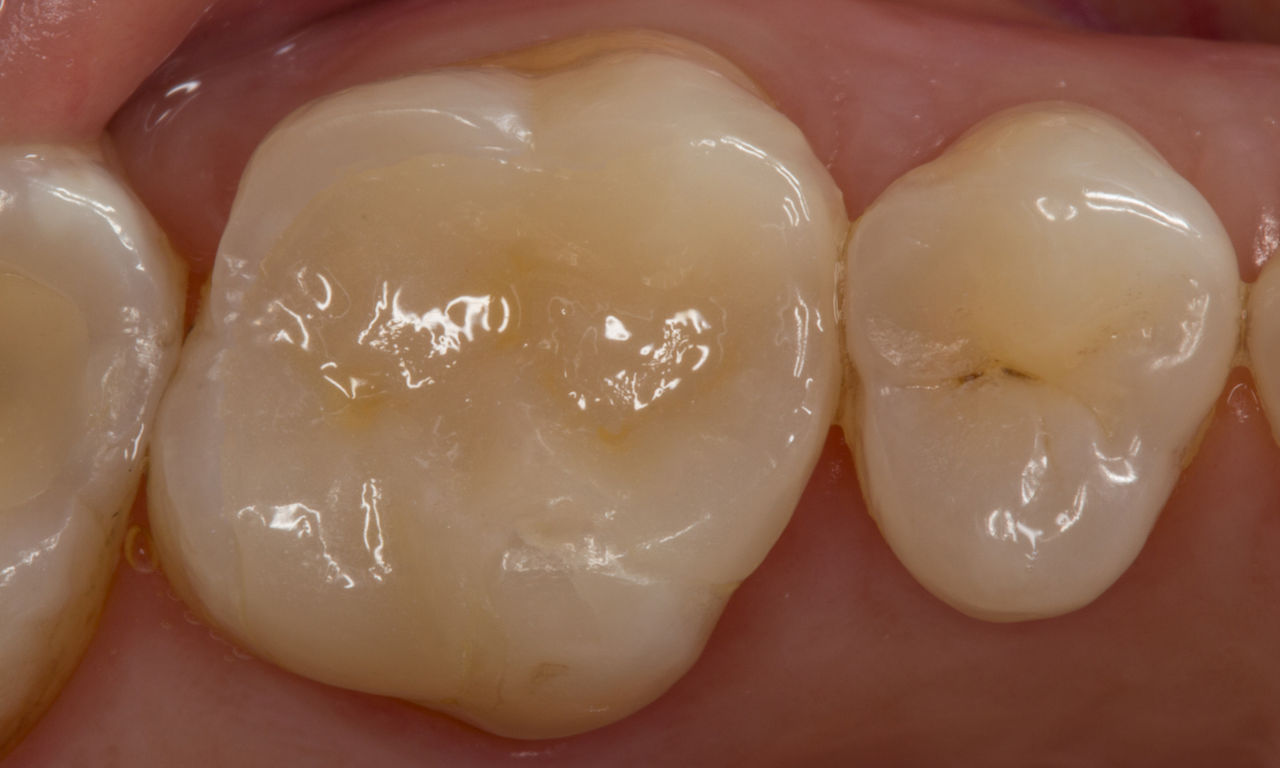

Première molaire supérieure, en 100 minutes

Un inlay CEREC Tessera

La restauration lors d’une consultation unique s’est avérée être une solution particulièrement efficace et confortable pour cette patiente, qui devait effectuer un trajet de 50 kilomètres pour se rendre au cabinet. Un inlay très esthétique a pu être réalisé avec CEREC Tessera.

Avant : Restauration en céramique fracturée réalisée à partir d’une vitrocéramique renforcée à la leucite après une durée d’utilisation clinique de 12 ans.

Après : Restauration fabriquée en consultation à partir d’une céramique avancée au disilicate de lithium CEREC Tessera.

Dr. Sven Rinke

Hanau, Allemagne